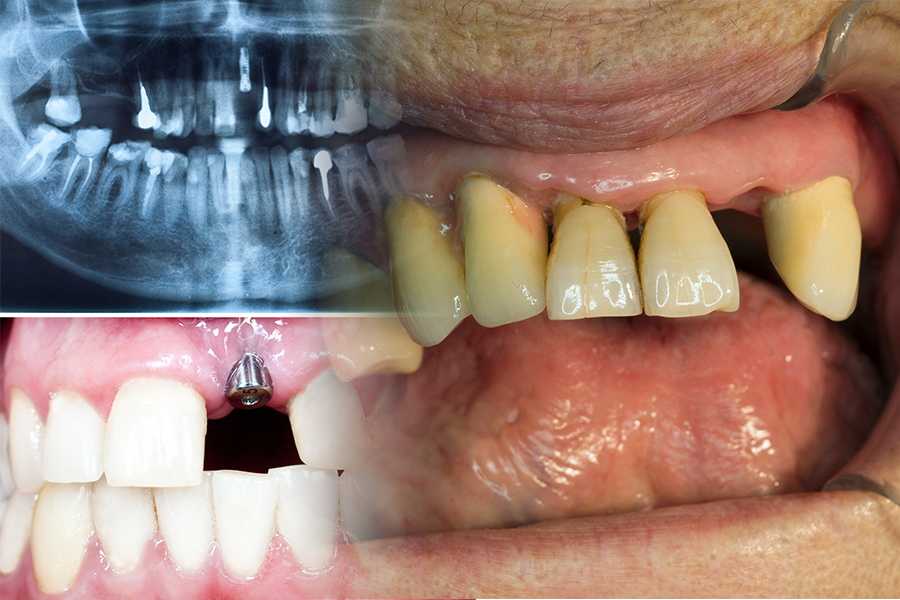

▶부분 무치악(완전 무치악 즉 이가 하나도 없는 경우는 보험이 적용되지 않음) 환자에 대하여 분리형(고정체와 지대주가 분리된 경우) 시술 재료를 사용한 경우만 보험 인정되고 인공 치근과 상부 보철이 한 개로 연결된 일체형은 보험 혜택을 받을 수 없다.

▶ 비귀금속 도재관(도자기와 금속을 녹여서 섞어 만든 치아모양의 보철 (Porcelain Fused to Metal crown) 보철 치료만 보험이 되며 지르코니아와 금 도재관은 보험이 되지 않는다.